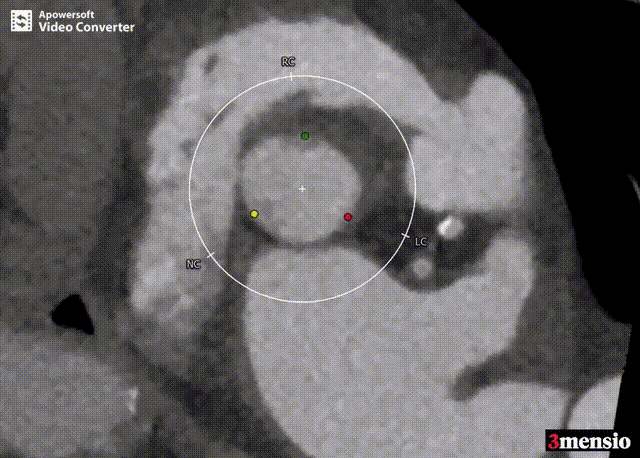

CT评估

术前分析及手术策略

患者瓣膜结构为三叶瓣,无明显增厚和钙化,法式窦结构,双侧冠脉开口高度可。升主动脉增宽,主动脉根部角度78°。主动脉瓣环周径78.8 mm,面积487.9 mm²,平均直径25.1 mm;左冠高度14.7 mm,右冠高度14.7 mm;左室流出道周径26.0 mm,主动脉窦管交界处(STJ)高37.5 mm。